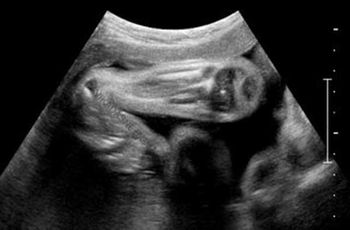

What is your diagnosis in this 3rd trimester fetus? Choose one from the following: